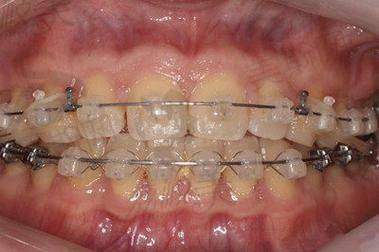

2. 技术水平:医院在牙齿矫正技术方面表现出色。涵盖了传统金属托槽矫正,包括普通金属托槽和金属自锁托槽;陶瓷半隐形矫正,有普通陶瓷托槽和陶瓷自锁托槽;隐形矫正,有国产的时代天使和进口的隐适美;还有舌侧矫正、儿童早期干预矫正、正畸正颌联合治疗等多种技术。能针对不同牙齿畸形情况提供合适的矫正方案。在种植等方面,医院使用高端材料,与瑞士Straumman亲水种植、德国强直等优质技术提供商形成战略合作伙伴,有相关技术支持。

陶瓷半隐形矫正:普通陶瓷托槽矫正15000元起,陶瓷材料的颜色与牙齿相近,美观度较高。陶瓷自锁托槽矫正18000元起,结合了陶瓷的美观和自锁托槽的优势,矫正成效更好。